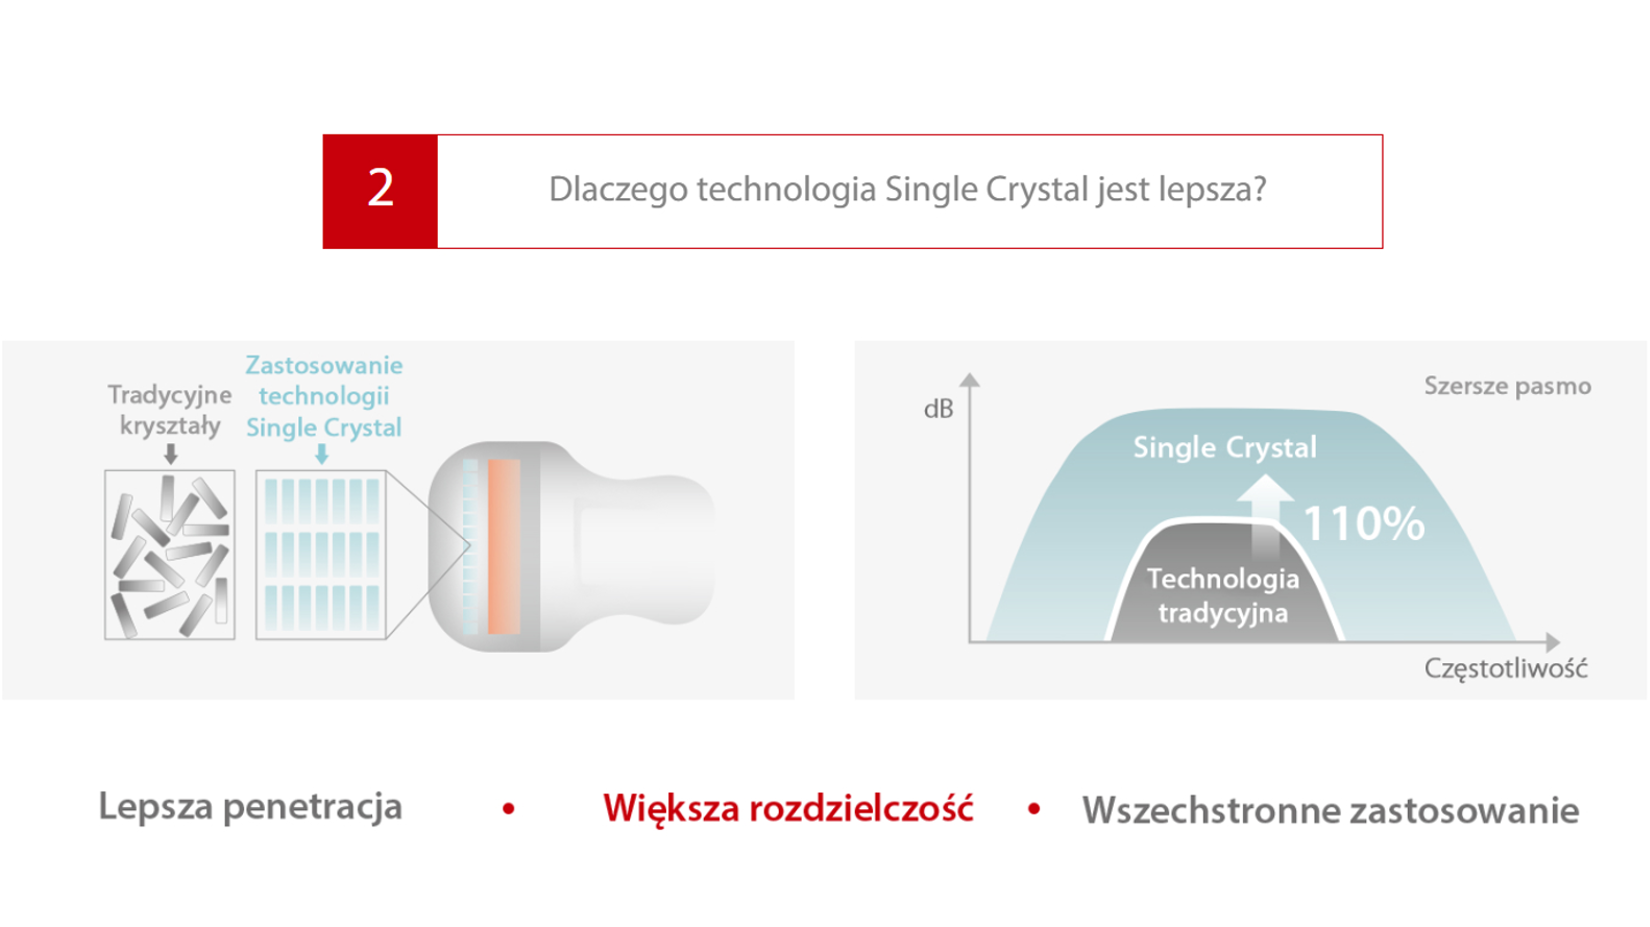

Obrazowanie Single Crystal

Obrazowanie Single Crystal

2